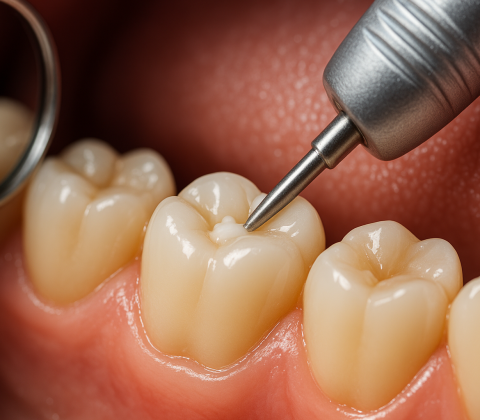

کفبندی در دندانپزشکی یکی از مراحل مهم در درمان پوسیدگیهای عمیق و آمادهسازی دندان برای ترمیم یا روکش است. این فرآیند به حفظ سلامت پالپ د